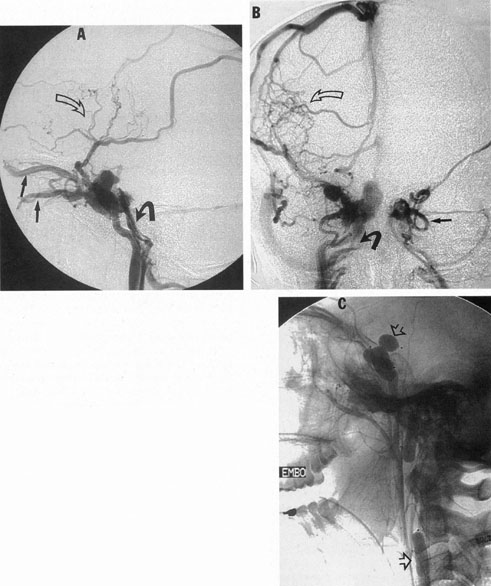

The therapy for AVMs has been reviewed elsewhere.91–93 The preferred treatment remains complete surgical excision of the malformation. However, significant advances in endovascular and radiosurgical techniques have resulted in a marked increase in the use of multimodal, staged approaches to AVM treatment. A variety of intravascular techniques use embolization91 with materials such as particles of polyvinyl alcohol (PVA), platinum coils, and injection of liquid N-butyl-cyanoacrylate (NBCA) adhesive (Fig. 11). Complications of intravascular embolotherapy include vessel perforation by the catheter, migration of embolic materials, and infarction and hemorrhage of normal brain.

Fig. 11. Embolization of middle cerebral vessels that supply occipital lobe arteriovenous malformation (AVM). The patient had a subarachnoid and intraparenchymal hemorrhage that produced a left homonymous field defect. A: Right carotid arteriogram demonstrates contribution via posterior communicating artery to a right occipital lobe AVM. B: Vertebral injection. The arrow points to the enlarged right posterior cerebral artery that is a major feeder of the AVM. C: Right carotid arteriogram during glue embolization procedure. The arrow points to a catheter as it traverses the segment seen in (B). The catheter was advanced via the internal carotid artery but is positioned far posteriorly. D: Upper branches to the AVM now are occluded, with residual low-flow vascularization via the middle cerebral artery. E: Skull film showing radiopaque glue within the AVM and blood vessels previously supplying it. The patient had a persistent visual field defect but greatly reduced headache and no persistence of subjective bruit. (Courtesy of Dr. Joseph Horton.)